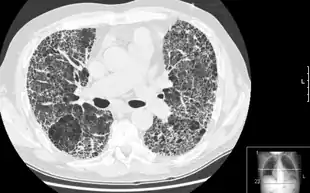

Pulmonary fibrosis is suggested by a history of progressive shortness of breath (dyspnea) with exertion. Sometimes fine inspiratory crackles can be heard at the lung bases on auscultation. A chest X-ray may or may not be abnormal, but high-resolution CT will frequently demonstrate abnormalities.[3]